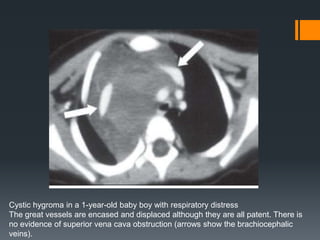

Cystic Hygroma/Lymphangioma

Cystic hygroma / lymphangioma is a benign proliferation of interconnecting

lymphatic vessels and sacs that may grow in an infiltrative fashion. It typically

affects infants younger than 6 months of age.

Mediastinal lymphangioma typically occurs in the superior aspect of the

anterior mediastinum and is usually contiguous with a cervical or axillary

component.

The mass usually appears as rounded, lobulated, multi-cystic tumour that can

reach a massive size. It tends to surround and displace mediastinal structures

and may infiltrate across tissue planes. The thin or thick septa may enhance

minimally after contrast administration .

Due to its infiltrating nature, complete surgical resection may be difficult and

close follow-up is needed to check for recurrence.

Cystic hygroma in a 1-year-old baby boy with respiratory distress

The great vessels are encased and displaced although they are all patent. There is

no evidence of superior vena cava obstruction (arrows show the brachiocephalic

veins).